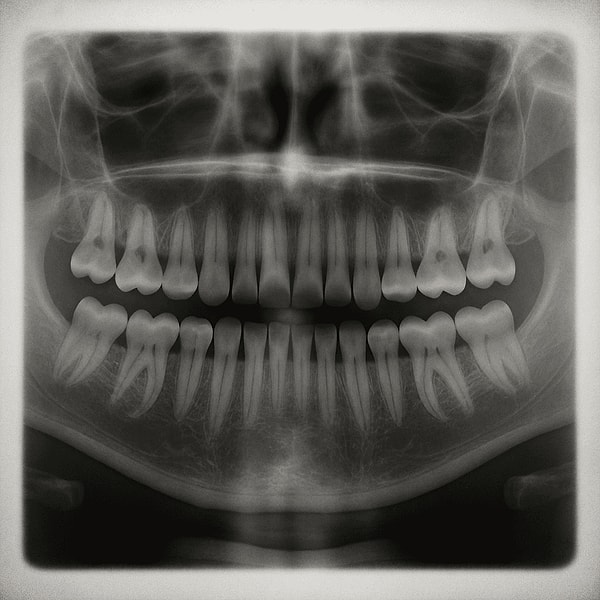

Şimdi Dişçiler Düşünsün: Japon Bilim İnsanları Dişleri Yeniden Çıkarmayı Sağlayacak İlaç Geliştirdi

Dişçi randevularının herkesin kabusu olduğu bu günlerde Japonya’dan bilim dünyasını çalkalayan bir gelişme gündemde. Araştırmacılar, insanların üçüncü kez diş çıkarabilmesini sağlayacak bir ilaç üzerinde çalışıyor ve bu mucizevi tedavinin 2030 yılına kadar herkesin erişimine sunulması hedefleniyor.

2021’de Scientific Reports dergisinde yayımlanan bir çalışmada, USAG-1 geninin ürettiği proteini hedef alan bir ilacın hayvanlarda yeni diş oluşumunu etkileyebileceği gösterilmişti. Bu protein diş büyümesini sınırlıyor; dolayısıyla proteinin engellenmesi, yeni dişlerin çıkmasına olanak tanıyor.

Ayrıca insanların ağız yapısında üçüncü bir diş setinin temellerinin halihazırda bulunduğu düşünülüyor. Bu durum, fazladan diş çıkaran hiperdonti vakalarında da gözlemleniyor. Bilim insanları, bu uyuyan diş tomurcuklarının genetik olarak yeniden etkinleştirilebileceğine inanıyor.